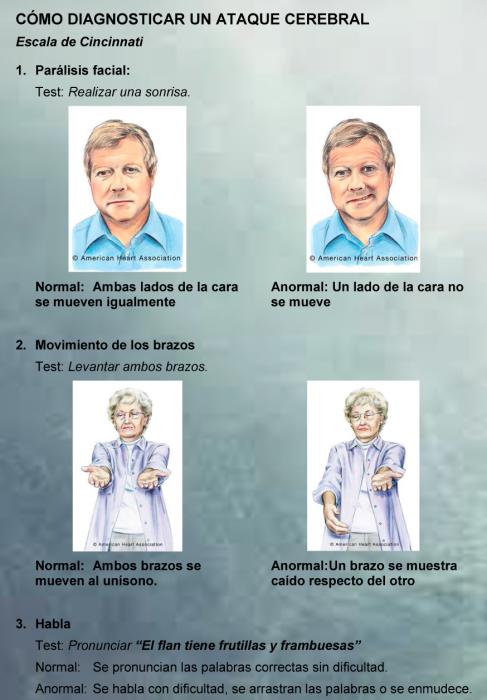

Para reducir la mortalidad y la discapacidad que causada por los ataques cerebrales es indispensable conocer los síntomas y minimizar los tiempos de consulta.

• Parálisis motora en la mitad del cuerpo. “Es la aparición repentina de la dificultad para mover la mano, la pierna, la cara torcida, la boca desviada. A esto llamamos hemiparesia o hemiplejía”, señaló el neurólogo.

• Dificultades en el lenguaje. Las personas que lo sufren tienen problemas para hablar.

• Alteraciones visuales. Visión borrosa, pérdida de visión o visión doble.

En general, la persona que sufre el ACV, no esta completamente lúcida. Difícilmente pueda resolver por sí mismo la situación. El conocimiento debe estar a cargo de las personas que lo rodean. Por lo general son los familiares los que reaccionan ante esta situación. Es importante reconocer los síntomas y llamar rápidamente a un servicio de emergencias médicas.